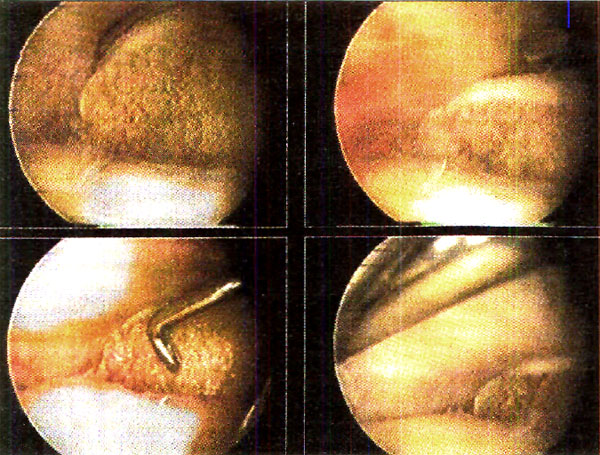

Los reparos utilizados para la reducción de la meseta tibial son el borde sano del cartílago y la cara inferior y el borde libre del menisco.(Fotos 2)

Foto 2: Parámetros de reducción de la fractura

La posición de los tornillos es controlada mediante intensificador de imágenes. La asistencia artroscópica nos permite controlar que el injerto no migre dentro de la articulación. Por último también evaluamos que los fragmentos fracturarios no se desplacen al realizar movimientos de flexo-extensión de rodilla luego de realizada la osteosíntesis.